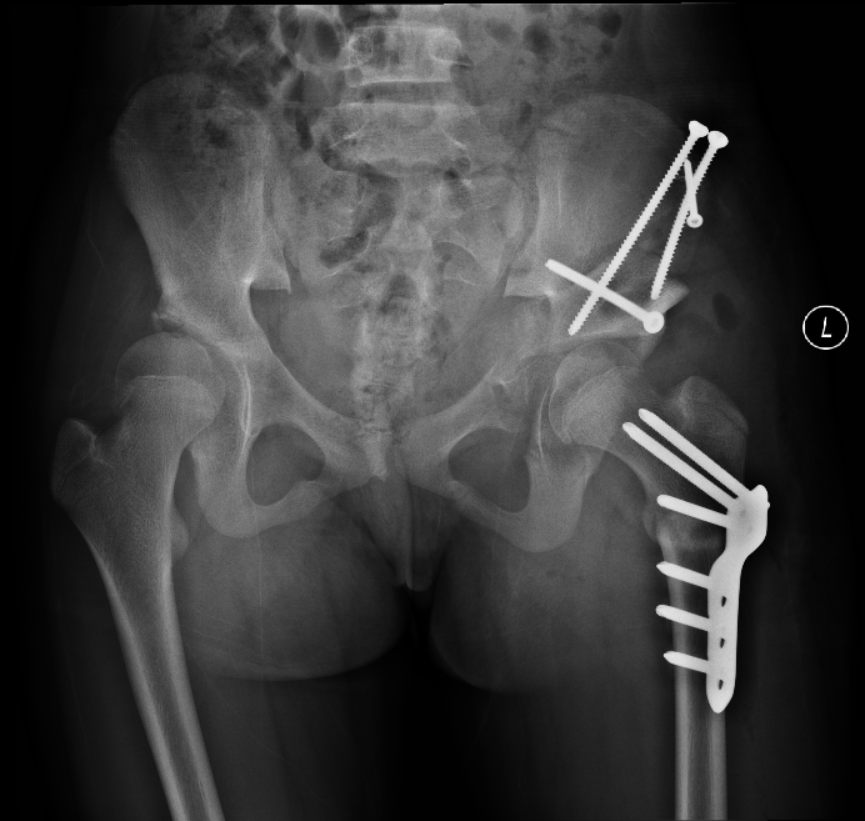

2018-11 髋臼PAO截骨术后第3天:双髋关节正位X线片

2019-09 左侧髋臼PAO截骨术后第3天:双髋关节正位X线片,右侧术后10个月